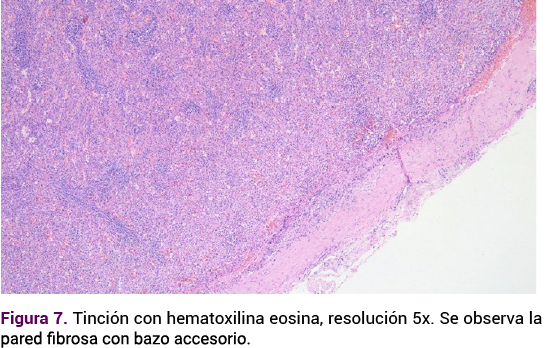

<strong>Figura 7</strong>

Figura 7. Tinción con hematoxilina eosina, resolución 5x. Se observa la pared fibrosa con bazo accesorio.